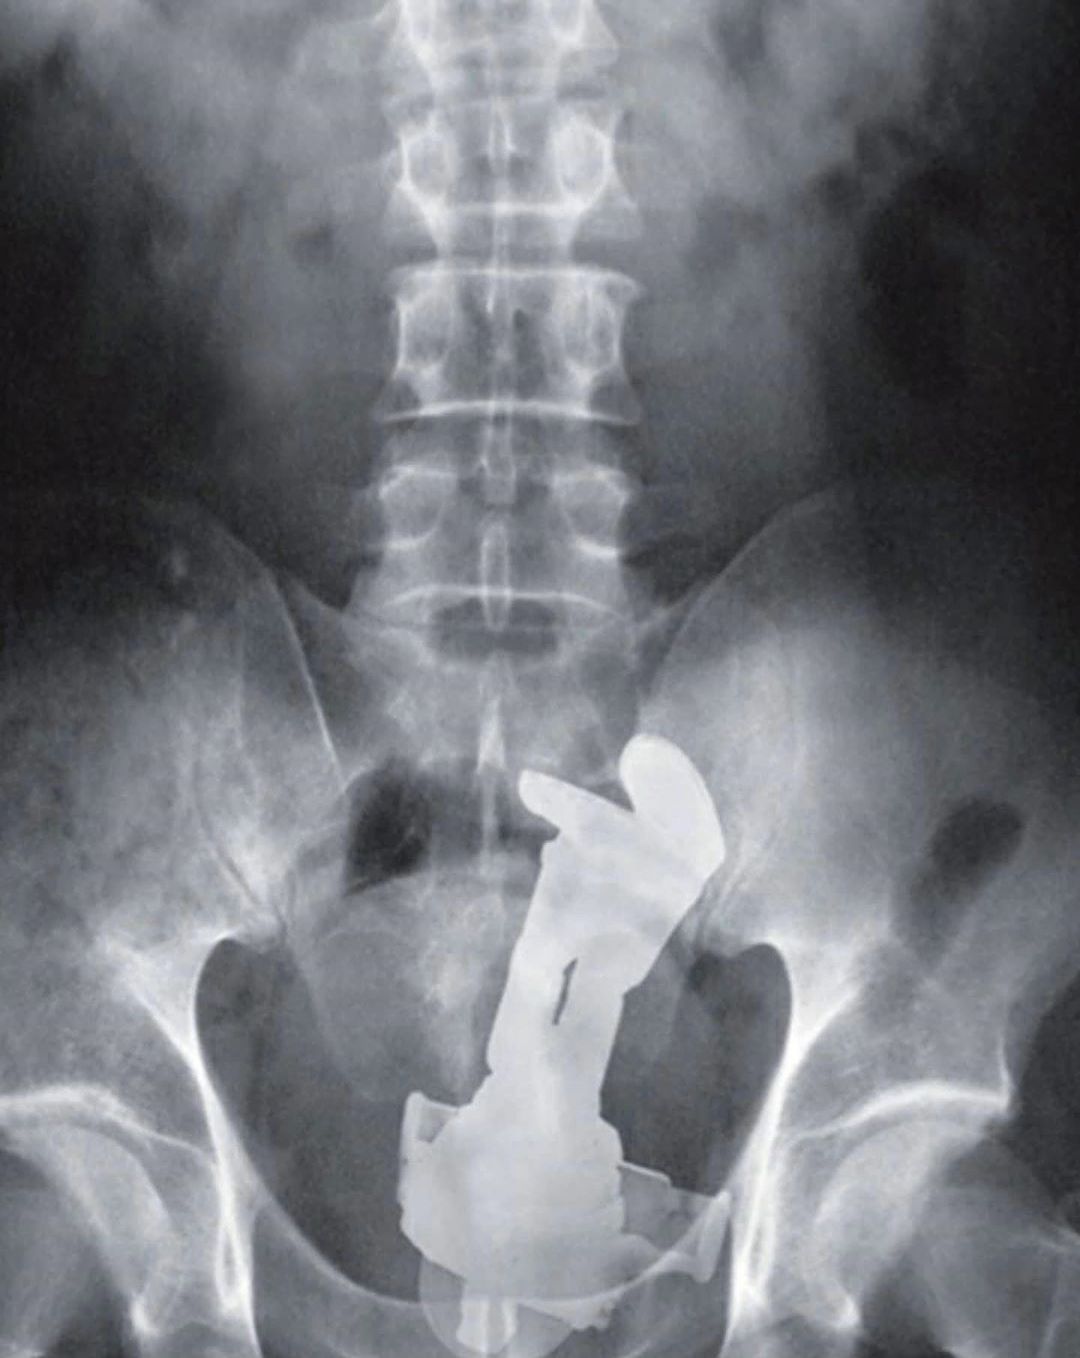

This is an actual emergency room X-ray. Patient explained that the toy got lodged and stuck when it was inserted and a button was accidentally pushed, extending out the wings. The majority of cases of rectal foreign bodies are the result of insertion during erotic activity. Typically found objects are vibrators, dildos, light bulbs, candles, shot glasses, and bottles. Some rectal foreign bodies may have been initially swallowed but later present with complications in the rectum. Patients may be very embarrassed to disclose the circumstances regarding the foreign body insertion, and there may have been multiple attempts at self-removal. Typical clinical findings of a rectal foreign body are pain with defecation, abdominal pain, rectal bleeding, pruritus, and constipation. Delays in seeking medical attention and multiple attempts at self-removal can lead to mucosal edema and muscular spasms, making removal of the object more difficult. The removal of some objects are challenging depending on the shape, material and orientation within the rectum. The object in this case is removed by using a long surgical forceps.

It appears to be inserted feet first, head down like a birthing baby. Indeed it does appear to be a buzz light year figurine. Oh dear.